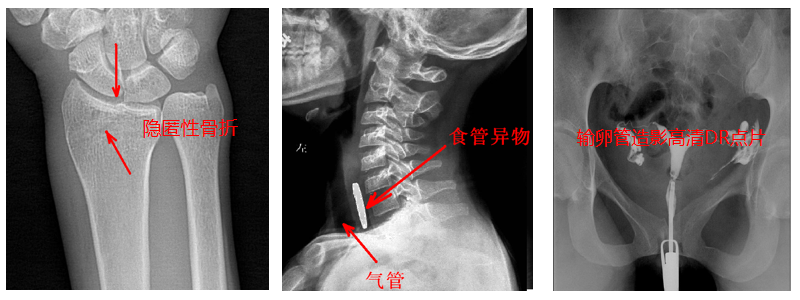

2.数字透视。适用于全身各部位透视(如胸透、腹透等),以及在透视下DR点片等;动态采集速度≥25帧/秒,应用于消化科、泌尿科、妇科等。

4.数字造影。PLD5500B动态DR机适用于各种普通及特殊造影,如口服胆囊造影、静脉胆道造影、T管造影、逆行胰胆管造影(ERCP)、静脉肾盂造影(IVP)、子宫输卵管造影、脊髓造影等,主要应用于消化内外科、泌尿外科、妇科、神经内外科等。

5.准确点片。在透视下准确找到病灶部位,这对于早发现隐匿性骨折有着不可替代的作用。更难能可贵的是,它可以在透视情况下进行整骨复位以及术后在透视下检查。